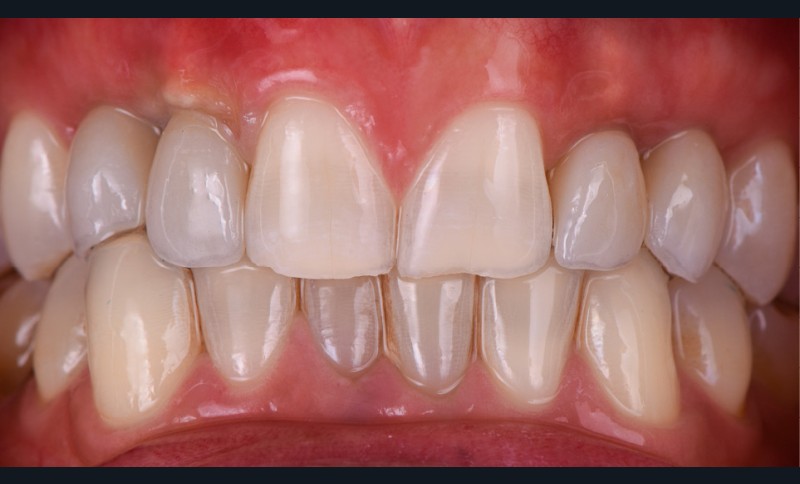

- pose des couronnes d’usage selon le protocole classique (fig. 9 et 10a) ;

Ce cas clinique met en exergue les possibilités grandissantes qu’offre le flux digital dans la prise en charge du secteur antérieur [3]. Ce dernier confère précision et prédictibilité du résultat final, tant pour le praticien (guide chirurgical) que pour le patient (modélisation via un wax-up numérique). L’alliance du numérique et de la chirurgie dans un contexte particulier d’agénésie avec une occlusion perturbée permet de répondre aux doléances fonctionnelles et esthétiques du patient avec une prothèse parfaitement intégrée aux tissus périphériques dentaires et muqueux.